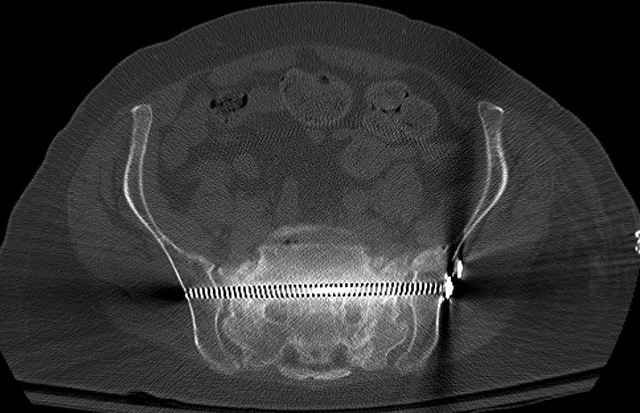

Here are a recent patient’s example slides...

54 yo Female Fell c/o Pain

3 Months After Fall

Continued Pain & Immobility

(+) Instability to Compressive Manual Exam

Pelvic CT Scan - 3 Months After Fall

Sacral Injuries

Ramus Fractures

Percutaneous Fixation

(B) Ramus-Retrograde

2 TransIliac-TransSacral

Upper Segment

mlcr